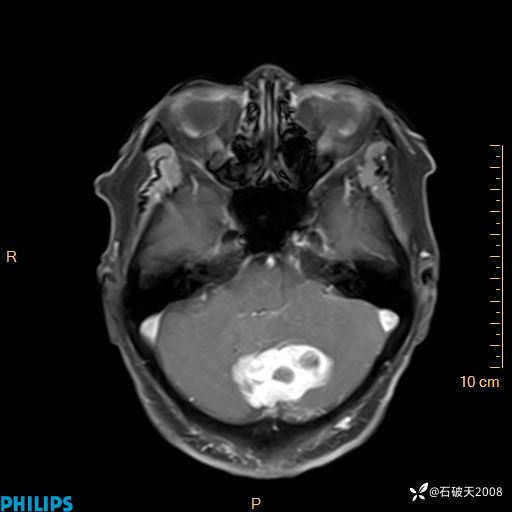

书上说这个肿瘤发生在幕下仅4.09%,你会想到它吗?(病理已公布)

女 86岁 主 诉:乏力1月

现病史:患者1月前活动出现双下肢乏力,无头晕、头痛、恶心、呕吐、肢体活动不利,休息后缓解,间断断发作,症状进行性加重,在家口服药物治疗(具体不详),效差,为进一步诊治,来我院,门诊按“乏力”收住我科,患者自发病以来,神志清,精神稍差,饮食睡眠欠佳,大小便正常,体重未见明显改变。

T2